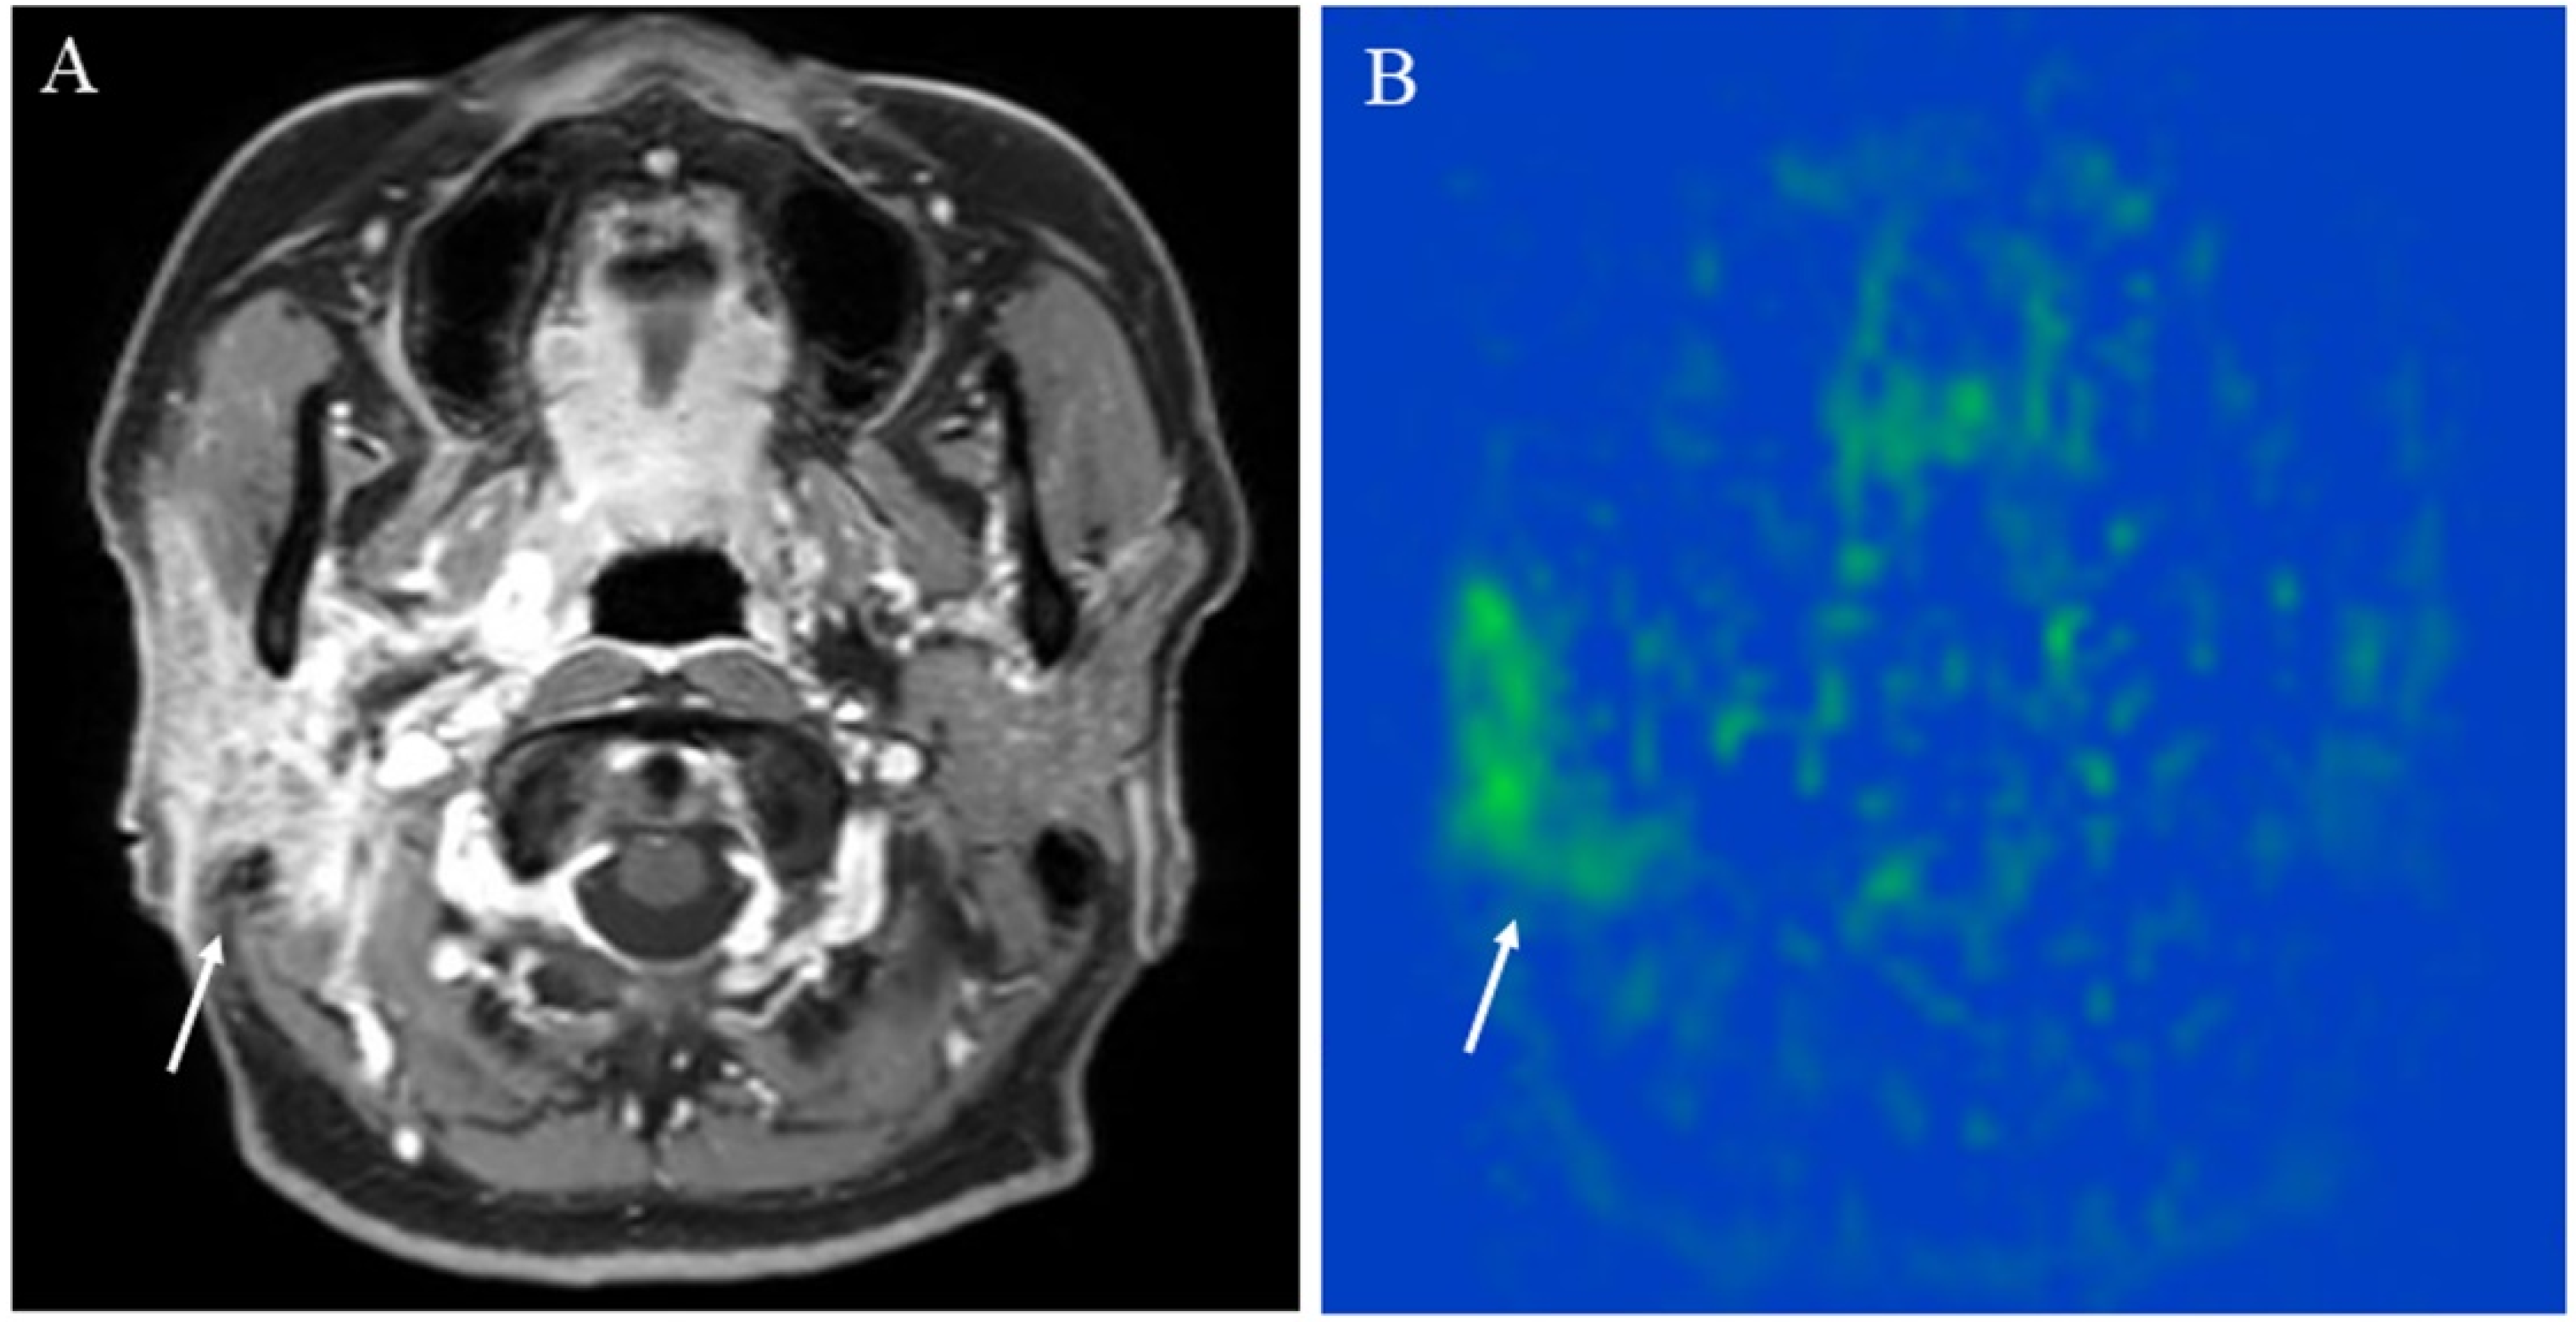

5.1.1. Inflammatory Lesions: Sialadenitis and Dacryoadenitis

5.1.2. Hypervascular Lesions

5.1.3. Salivary Gland Tumor Differentiation: Malignant Salivary Tumors, Pleomorphic Adenomas, and Warthin’s Tumors

5.1.4. Other Head and Neck Tumors